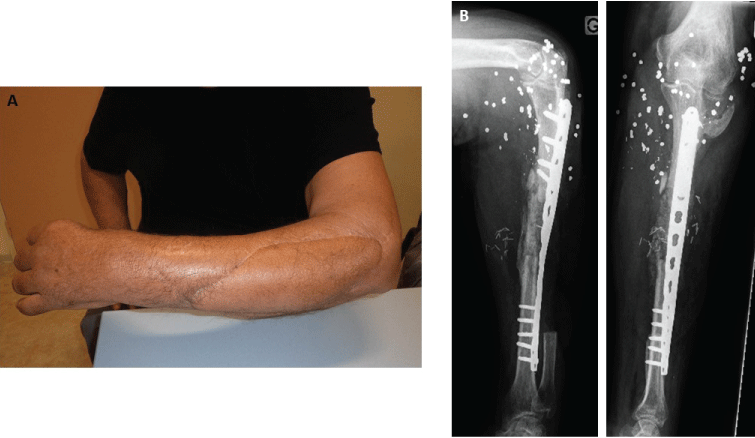

At the last follow-up of 8 months, cosmetic aspect was excellent and bone union was achieved (Figure 5). The patient had full range of motion of the elbow and wrist, but presented a limited extension of the fingers. He was very satisfied of the functional outcome and declined tendon transfer surgery.

Figure 5: A) Aesthetic appearance after 8 months; B) Radiographs showing bone union at the last follow-up. View Figure 5